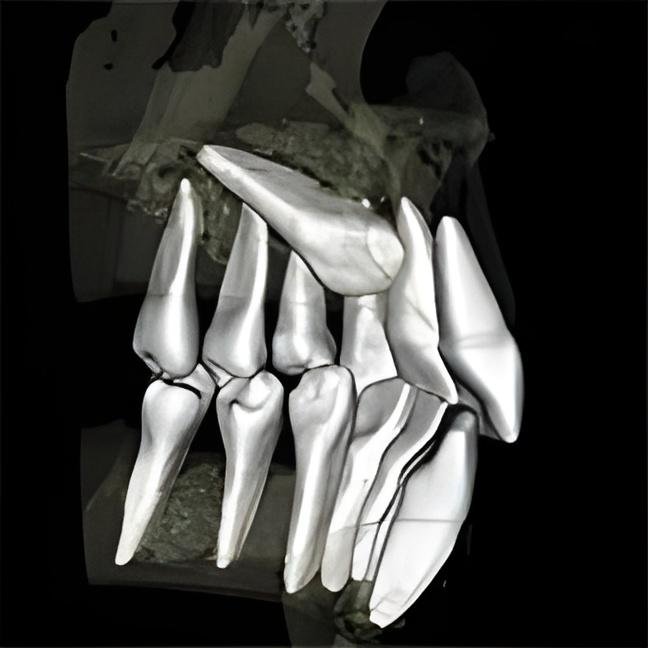

Tomografia komputerowa 3D (CBCT):

Nowoczesny gabinet stomatologiczny z obrazem 3D szczęki na tablecie, wykorzystywany przez stomatologa do analizy stanu zębów pacjenta.

Tomografia szczęki: szczęka w całości (planowanie wielu implantów), sektor przedni szczęki (od kła do kła), sektor boczny szczęki (jeden bok), tomografia zatoki szczękowej (ocena przed sinus-liftem)

Tomografia żuchwy: żuchwa w całości, sektor przedni żuchwy, sektor boczny żuchwy, ocena kanału nerwu żuchwowego

Tomografia specjalistyczna: oba stawy skroniowo-żuchwowe (TMJ), tomografia przed ekstrakcją zęba zatrzymanego, tomografia w endodoncji (ocena skomplikowanych kanałów), tomografia w periodontologii (ocena ubytków kostnych)

Tomografia zatokowe: zatoka szczękowa prawa, zatoka szczękowa lewa, obie zatoki szczękowe, tomografia przed operacją zatokową